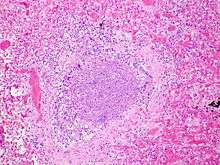

.jpg)

The term usually refers to acute viral bronchiolitis, a common disease in infancy. This is most commonly caused by respiratory syncytial virus[11] (RSV, also known as human pneumovirus). Other viruses which may cause this illness include metapneumovirus, influenza, parainfluenza, coronavirus, adenovirus, and rhinovirus.